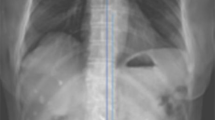

Radiographic evaluation (Fig. 1)

Spinal parameters on standing radiograph. Thoracic kyphosis (TK) and lumbar lordosis (LL) are defined as the angle between the cranial endplate of Th1 and the caudal endplate of Th12, the cranial endplate of L1 and the caudal endplate of L5, respectively. Sacral slope is defined as the angle between the sacral endplate and the horizontal plane. Sagittal vertical axis (SVA) is distance from C7 plumb line from the center of the C7 to the posterior edge of the upper sacral endplate. Pelvic tilt (PT) is defined as the angle is between the line connecting the midpoint of S1 endplate to the center of the femoral head and the vertical line of S1 endplate. Pelvic incidence (PI) is defined as the angle between the line perpendicular to the middle of the cranial sacral endplate and the line joining the middle of the cranial sacral endplate to the center of the femoral head axis.

All patients underwent conventional radiography in the standing position. For lateral films, the patients stood with their knees locked, with feet shoulder-width apart, and looking straight ahead. Measured parameters of interest included coronal Cobb angle between the superior edge of L1 and S1, lumbar lordosis (LL), thoracic kyphosis (TK), S1 slope (SS), sagittal vertical axis (SVA), pelvic tilt (PT), pelvic incidence (PI), the presence of spondylolisthesis (anterior slip > 3 mm), and the lumbar range of motion (ROM) defined as the difference in lumbar lordosis angle between flexion and extension. Spinopelvic mismatch was determined when PI-LL is more than 10°25.